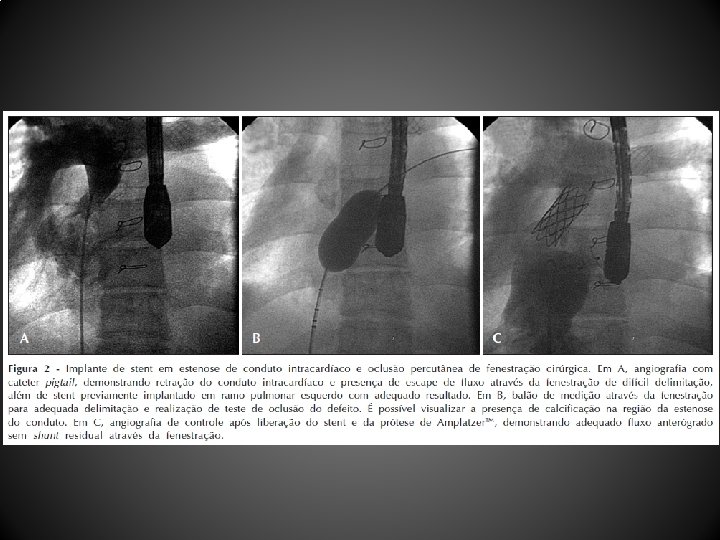

Procedimento e técnica • Oclusão de fenestrações • Acesso femoral para avaliação hemodinâmica e angiográfica completa do circuito de Fontan • Saturações venosas sistêmicas e pressões em todo o circuito • Angiografias com cateter Berman em veias cavas superior e inferior e artérias pulmonares para avaliar a morfologia do circuito de Fontan e para definir a localização da fenestração cirúrgica além de possíveis vasos venosos colaterais

Procedimento e técnica • Após cruzar a fenestração, guia extrarrígida posicionada nas veias pulmonares ou na cavidade atrial, através da qual balão de medição insuflado para teste de oclusão da fenestração com monitorização de saturação arterial de oxigênio bem como de pressão arterial sistêmica e de enchimento • Na ausência de aumento significativo da pressão venosa sistêmica, queda da saturação de oxigênio ou sinais de baixo débito cardíaco, deu-se prosseguimento à oclusão da fenestração com prótese de Amplatzer

Resultados • Entre abril de 2004 e dezembro de 2010, 12 pacientes (média de idade, 103, 1 + 88, 6 meses; peso, 29, 9 + 12, 7 kg) submetidos a CF (10 tubos extracardíacos, 2 túneis intra-atriais) foram tratados 44, 1 + 26, 7 meses após a CF • Um paciente não tolerou o teste de oclusão com o balão, sendo contraindicado o procedimento • As próteses utilizadas foram: Helex. TM (4 pacientes), Amplatzer. TM (2 pacientes), Cardia Atriasept. TM (2 pacientes), Figulla. TM (1 paciente), Cera. TM (1 paciente), e 1 stent coberto Cheatham-Platinum. TM • Após a oclusão da fenestração, a saturação de oxigênio aumentou significativamente (82, 1 + 6, 5% para 95, 2 + 3, 2%), sem aumento significativo da pressão venosa central (12, 4 + 2, 6 mm. Hg para 14, 5 + 2, 3 mm. Hg) nem queda do débito cardíaco • Após o procedimento foi observado shunt residual imediato em 5 pacientes, que desapareceu antes da alta